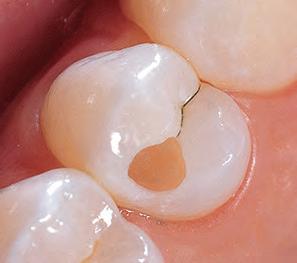

Sable Seek caries indicator contains FD&C dyes, and Seek caries indicator contains D&C dyes in a glycol base. Both are used to stain carious and demineralized dentin.

Seek and Sable Seek caries indicators stain carious and demineralized dentin and can be very useful for difficult-to-see areas, for example; undercuts of preparations, dark dentin, areas along the DE junction, etc. Green Sable Seek caries indicator helps visualization of decay in deep caries cases to help avoid pulp exposures.

PROCEDURE

dentin) with slow-speed round bur or excavator. To control overexcavating near the pulp, remove final portion of caries with hand excavator.